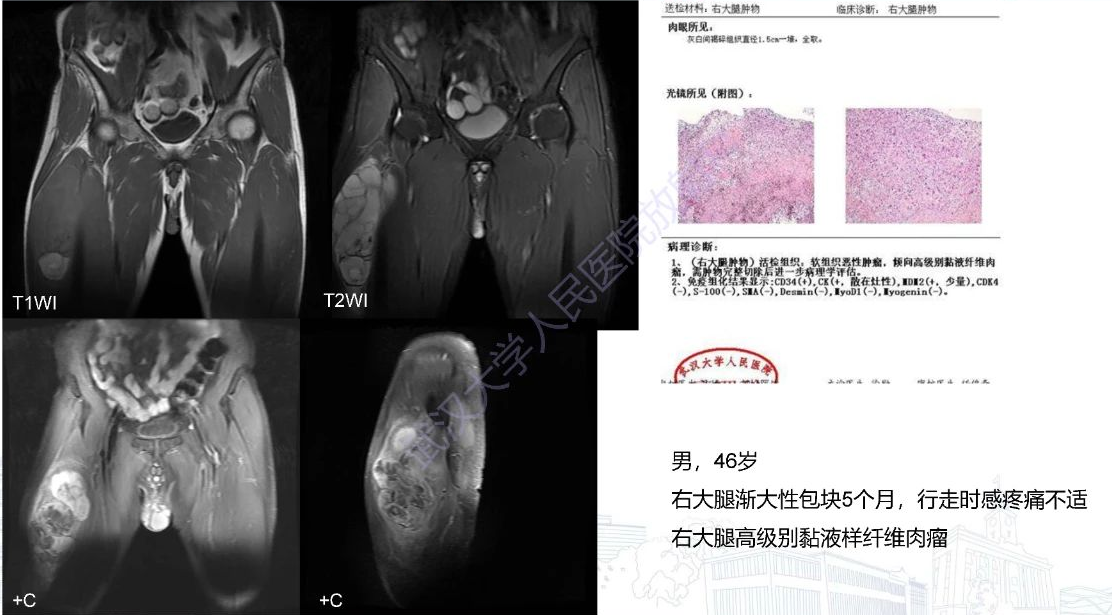

3.粘液样纤维肉瘤:多见于中老年人,下肢多见,位置表浅,呈膨胀性生长;MRI表现为不均匀混杂信号,T1WI以等信号为主,夹杂等、高信号(出血),T2WI呈高信号,夹杂散在等低信号的纤维成分;增强扫描呈

不均匀强化。